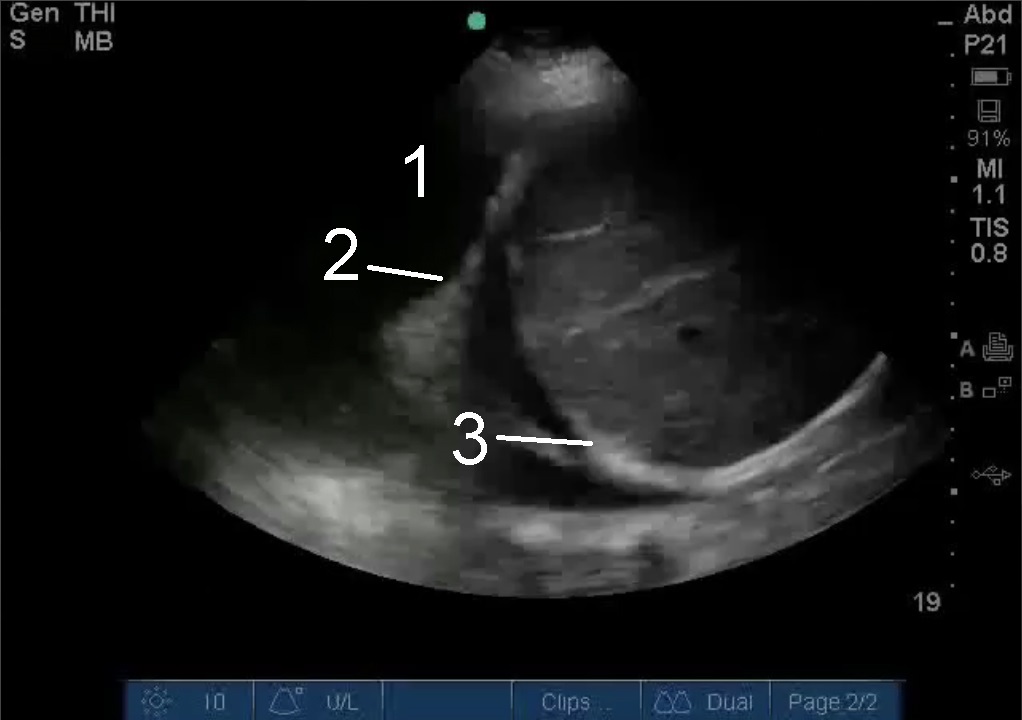

胸腔穿刺手順肺の画像

胸水

肺の先端

横隔膜